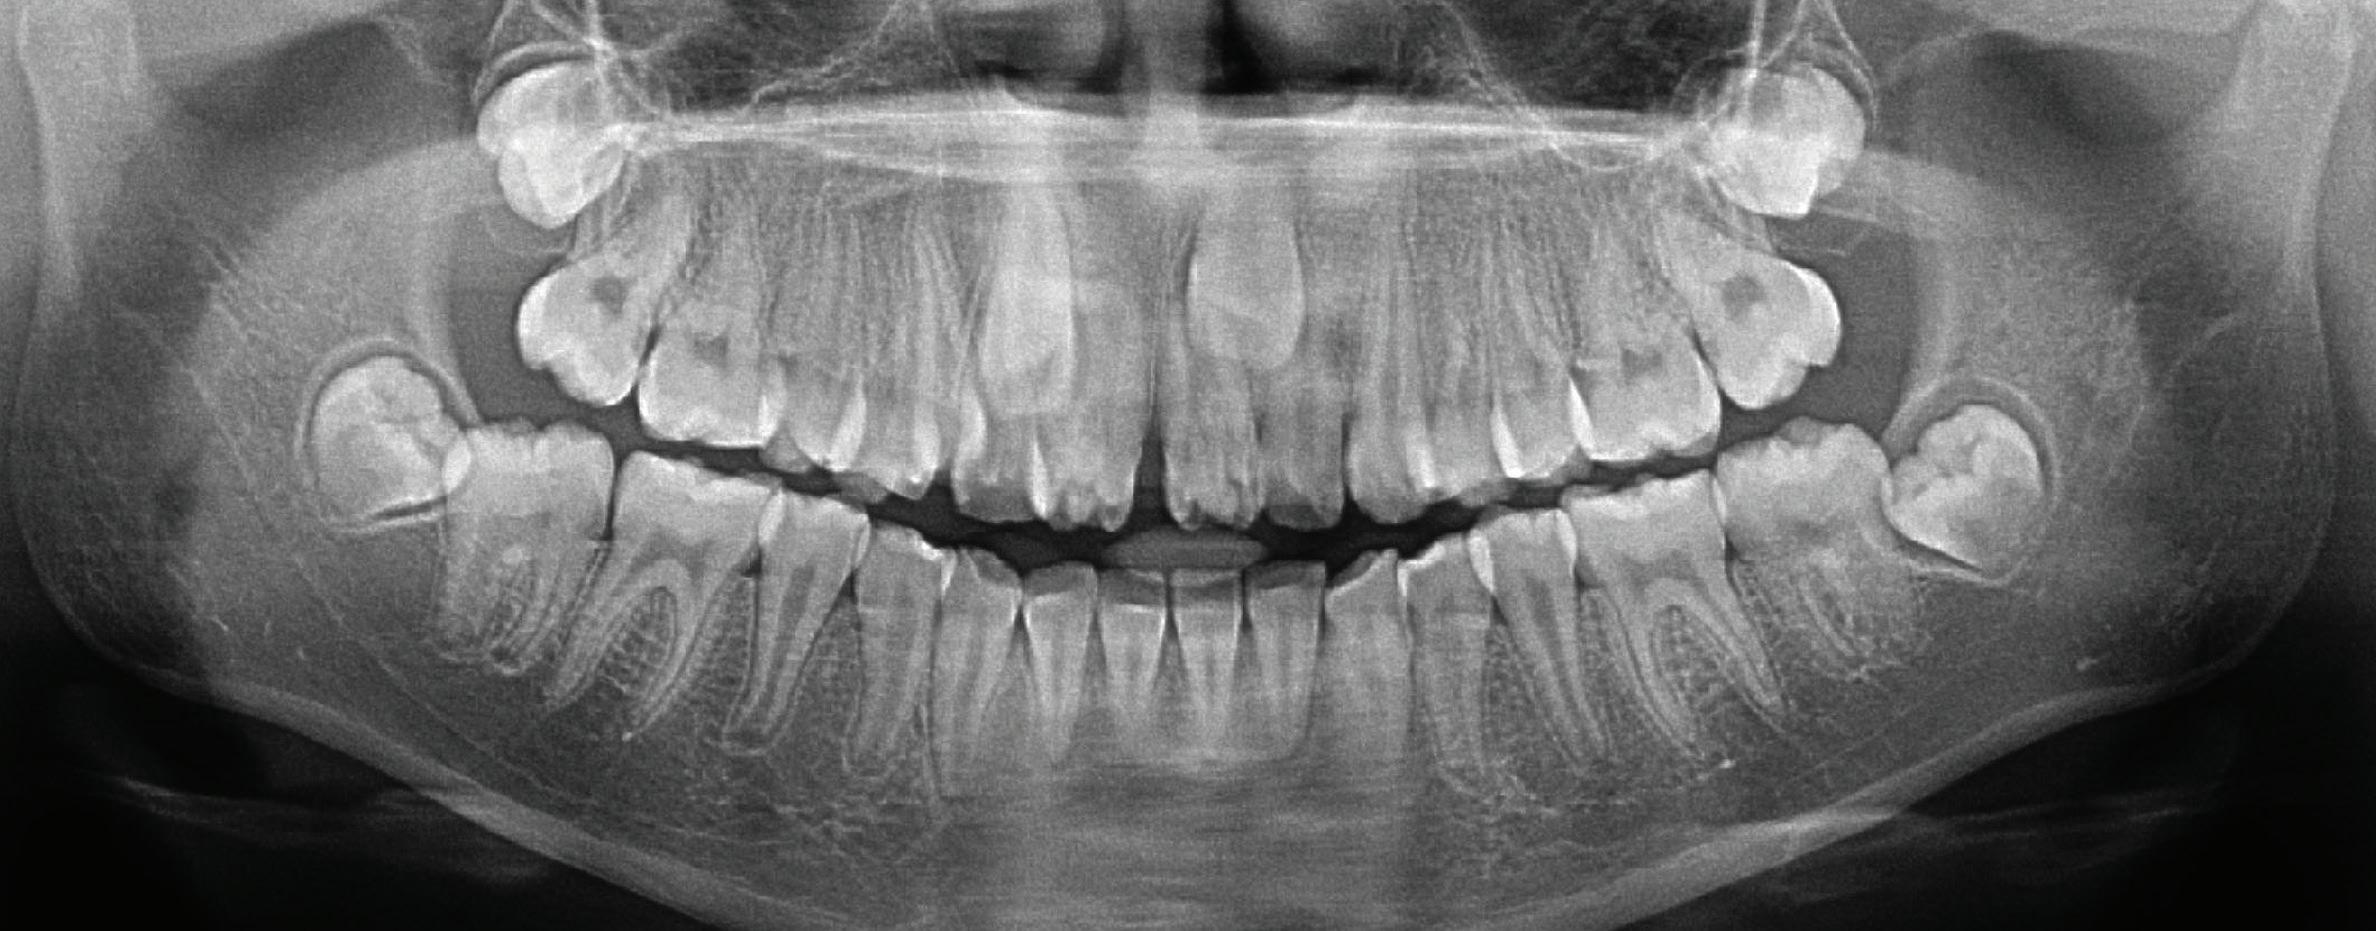

The patient did not present for the 6-month recall but did present 19 months after partial pulpotomy for an orthodontic consultation at the orthodontic clinic of the same institution. At this visit, the patient reported no complaints of spontaneous or stimulated pain. Continued root development of the mandibular right first molar was noticeable in the panoramic radiograph ordered by the orthodontist, indicating that the treatment was successful (Fig 5).

Fig 5. Cropped panoramic radiograph 19 months after partial pulpotomy, revealing continued root development.